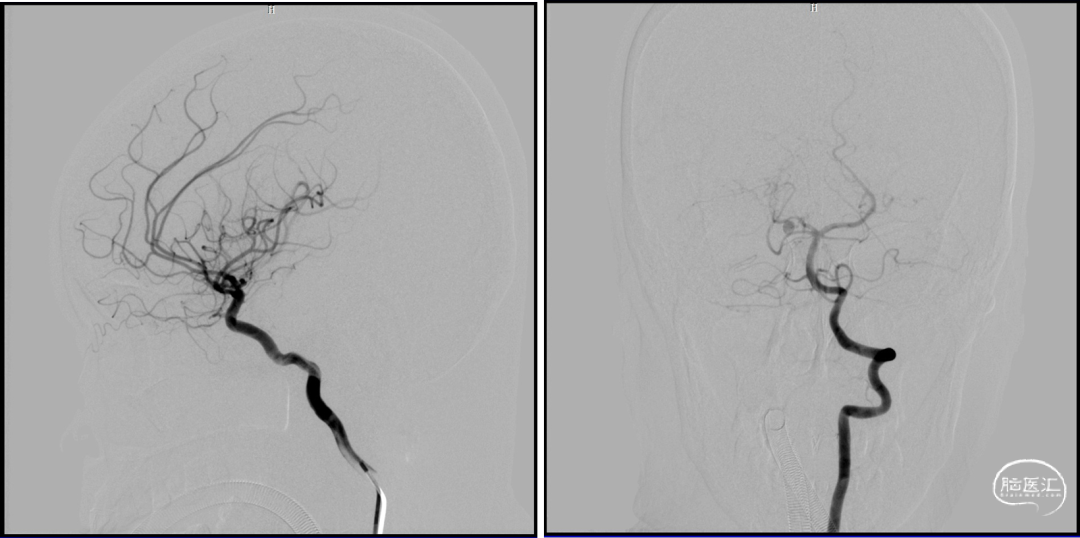

微导管超选

球囊保护下微导管造影证实假性动脉瘤

球囊保护下25%gb栓塞

2023-08-30

术后造影:假性动脉瘤消失